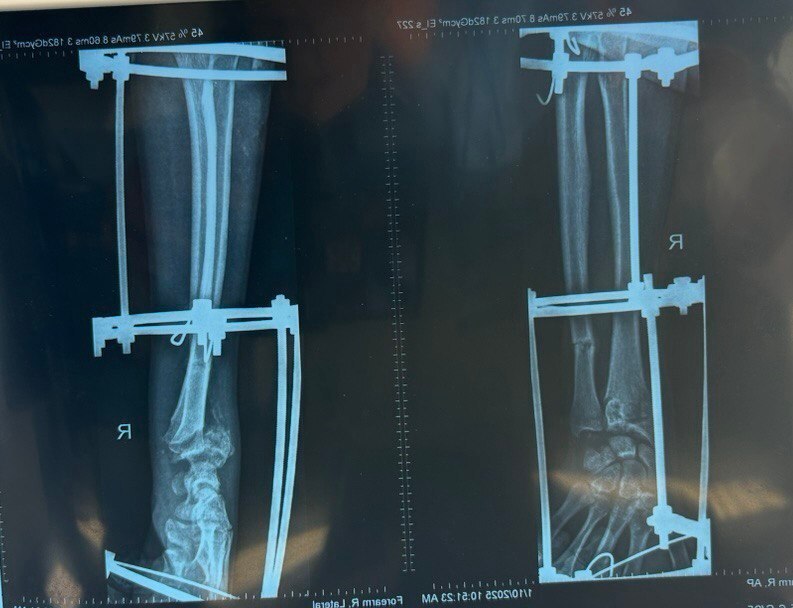

Путь к выздоровлению занял месяцы и состоял из нескольких сложнейших этапов. Медики провели пересадку кожи на обширный ожог, собрали сломанные кости бедра и голени с помощью металлоконструкций. Для сращения кости предплечья применили аппарат Илизарова, который постепенно, месяц за месяцем, восстанавливал правильное положение отломков.

На последнем этапе врачи демонтировали аппарат и выполнили окончательную фиксацию. Но главным чудом, по словам медиков, стала невероятная воля к жизни самого пациента. Преодолев боль, воспаления и риск инфекций, он сделал свои первые шаги.